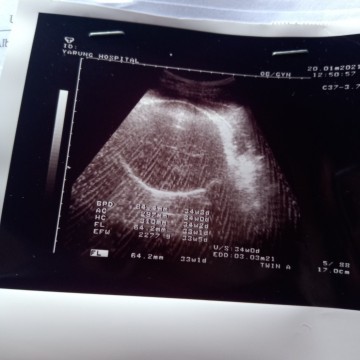

ขาวๆเป็นเส้นคือกระโหลกศีรษะ ในภาพเห็นเส้นรอบววศีรษะกับเส้นผ่านศูนย์กลางศีรษะ ไม่เห็นหน้าค่ะ

เราว่าไม่ใช่นะคะ ไม่ช่องท้องก็รอบศีรษะมากกว่า🤔🤔

ท้องน้องรึเปล่าคะ

หัว ของเด็กค่ะ

น่าจะหัวนะคะ

คิดว่าหัวค่ะ